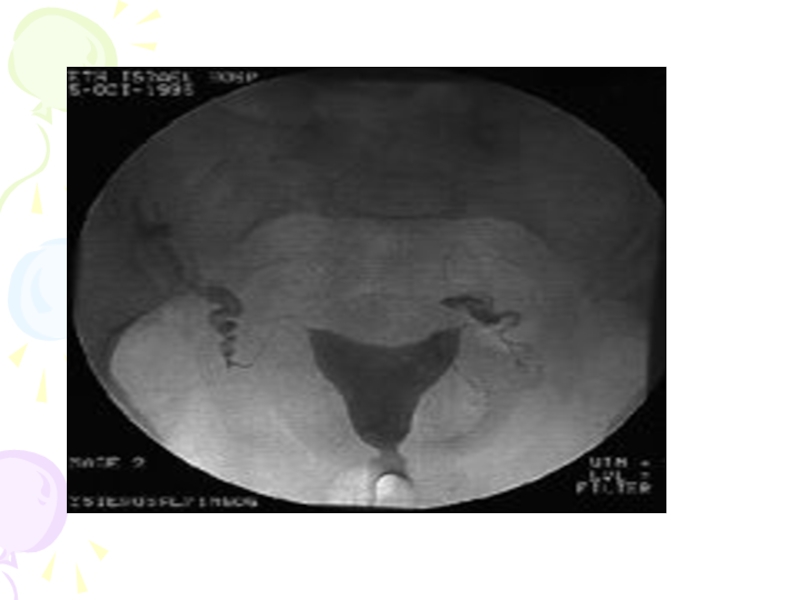

Слайд 10Гистеросальпингография

Метод, достаточно широко используемый в клинической практике для оценки состояния маточных

труб и наличия спаечного процесса в малом тазу, выявления пороков развития матки, гиперпластических процессов эндометрия, субмикозной миомы матки, внутреннего эндометриоза, внутриматочных синехий, истмико-цервикальной недостаточности.

Методы диагностики трубно-перитонеального бесплодия: 1. Клинико-анамнестические

данные, указывающие на перенесенный воспалительный процесс органов малого таза, аборты, чревосечение, ношение внутриматочный контрацептив. 2. Результаты влагалищного исследования, при котором определяется наличие спаечного процесса в малом тазу и изменение анатомического расположения матки и придатков. 3. Микроскопия и бактериоскопия влагалищного содержимого, содержимого цервикального канала и полости матки. 4. Исследование на наличие урогенитальной инфекции: хламидиоз, гарднереллез, уреаплазма, микоплазма, вирусы. 5. Гистеросальпингография для оценки состояния матки, проходимости маточных труб, наличия спаечного процесса в малом тазу (рис. 7.1-7.6). 6. Лапароскопия дает точную оценку состояния органов малого таза, состояния и проходимости маточных труб, степени распространения спаечного процесса в малом тазу.